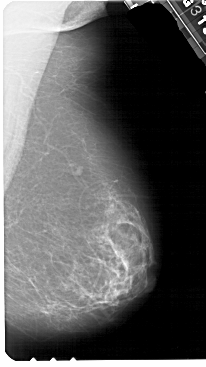

A_1552_1.LEFT_MLO

LEFT_MLO LINES 5491 PIXELS_PER_LINE 3436 BITS_PER_PIXEL 12 RESOLUTION 43.5 OVERLAY